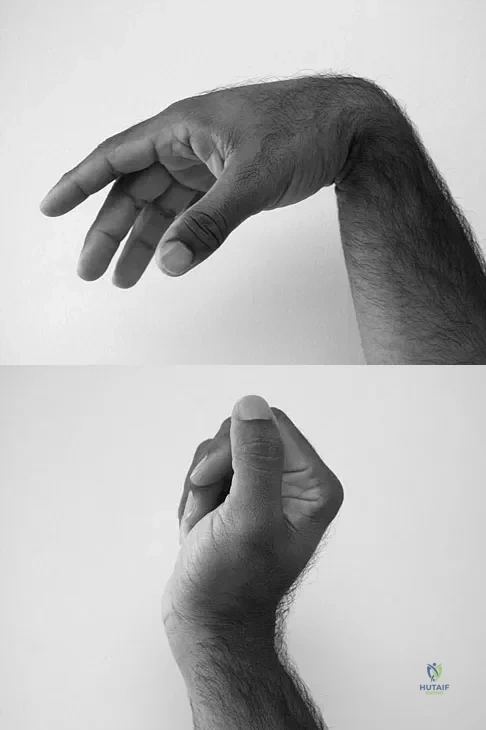

A 35-year-old man sustained a 1-inch stab incision in his proximal forearm while trying to use a screwdriver 2 weeks ago. The laceration was routinely closed, and no problems about the incision site were noted. He now reports that he has been unable to straighten his fingers or thumb completely since the injury. Clinical photographs shown in Figures 30a and 30b show the man passively flexing the wrist. What is the most appropriate management?

Explanation